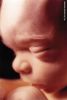

16. týden (Detail ucha)